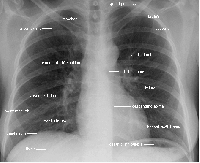

Расшифровка флюорограммы после прохождения флюорографии легких

Описание флюорограммы

Результаты флюорографии готовят обычно несколько дней, после этого полученную флюорограмму рассматривает рентгенолог. В том случае, если была проведена флюорография здоровых легких, на дальнейшее обследование пациента не отправляют. Если рентгенолог обнаружил изменения легочной ткани, человека могут отправить для уточнения диагноза на рентгенографию или в противотуберкулезный диспансер.

К снимку, полученному после флюорографии легких, прилагается заключение рентгенолога, в котором могут значиться такие формулировки:

- корни расширены, уплотнены . Корни легких формируют лимфатические узлы и сосуды, легочная вена и артерия, главный бронх, бронхиальные артерии. Уплотнение в этой области при общем удовлетворительном состоянии здоровья указывает на бронхит, воспаление легких и другие воспалительные, возможно хронические процессы.

- Корни тяжисты. Чаще всего такое заключение после проведенной флюорографии легких указывает на бронхит или другой острый/хронический процесс. Такое изменение легочной ткани часто обнаруживают на флюорографии легких курильщика.

- Усиление сосудистого (легочного) рисунка . Легочный рисунок образуют тени вен и артерий легких и если кровоснабжение из-за воспаления усилено, а это может и бронхит, и начальная стадия рака, и воспаление легких, на флюорографии заметно, что сосудистый рисунок слишком выделяется. Кроме этого, выявленное на флюорографии легких усиление рисунка может указывать и на проблемы сердечно-сосудистой системы.

- Фиброзная ткань . Обнаруженная соединительная ткань в легких говорит о том, что ранее человек перенес заболевание легких. Это могла быть травма, инфекция или операция. Несмотря на то, что подобное заключение указывает на потерю части легочной ткани, такой результат часто дает флюорография здоровых легких.

- Очаговые тени. Так называют затемнения области легких на флюорограмме размером до 1 см. Если очаги обнаружены в нижних и средних отделах легких, это может быть пневмония. На сильное воспаление указывает такая формулировка в заключении флюорографии легких: «неровные края», « слияние теней», «усиление сосудистого рисунка». Если же очаги больше ровные и плотные, значит, воспалительный процесс идет на спад. Если очаги обнаружены в верхних отделах легких, это может указывать на туберкулез.

- Кальцинаты. Так называют округлые по форме тени, напоминающие по плотности костную ткань. Опасности подобные явления не представляют, а лишь говорят о том, что у пациента был контакт с больным пневмонией, туберкулезом, зараженным паразитами и т. д., но организм не дал развиться инфекции, а изолировал бактерии-возбудители под отложениями солей кальция.

- Плевроапикальные наслоения, спайки . Обнаруженные на флюорографии легких структуры из соединительной ткани – спайки, в большинстве случаев также не требуют лечения, а лишь указывают на воспаление в плевре в прошлом. Иногда спайки вызывают болезненные ощущения, в этом случае следует обратиться за медицинской помощью. Плевроапикальными наслоениями называют утолщения верхушек легких, и они также указывают на то, что человек перенес воспаление, затронувшее плевру (чаще всего это туберкулез).

- Синус запаян или свободен. Плевральные синусы – это образованные плевральными складками полости. Если легкие здоровые, флюорография покажет, что синусы свободны. Но иногда наблюдаются скопление жидкости (в этом случае требуется лечение) или запаянные спайки.

- Изменения диафрагмы. Такое заключение после флюорографии легких дают в том случае, если у человека обнаружена аномалия диафрагмы, которая могла развиться из-за плохой наследственности, ожирения, деформации спайками, после перенесенных плеврита, болезней печени, пищевода, кишечника или желудка. В этом случае обычно назначают дополнительное обследование.

- Тень средостения смещена или расширена. Средостением называют пространство между легкими и органы в нем находящиеся - это аорта, пищевод, сердце, трахея, лимфатические сосуды, узлы, железа вилочковая. Расширение тени средостения наблюдается из-за увеличения сердца, гипертонии, сердечной недостаточности, миокардита. Смещение средостения может указывать на неравномерное скопление воздуха или жидкости в плевре, большие новообразования в легких. Подобное заключение флюорографии легких указывает на то, что необходимо немедленно пройти дообследование и лечение.